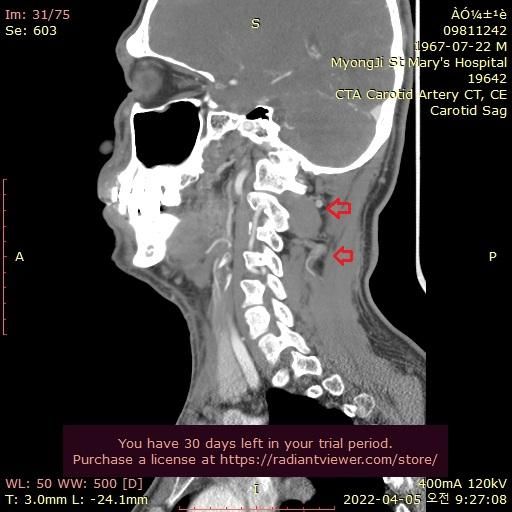

그런데 가까운 의원에서 그때의 영상을 보다가 그림과 같이 목 뒤쪽에 정맥혈관에 기형이 심한것을 알았습니다.

울퉁불퉁 하고 아주 굵어져서 혈액 순환이 안도는것으로 보입니다.

자료 찾아보니 심부경정맥 인것 같습니다. 내경정맥등과 함께 뇌의 혈액을 심장으로 빼내서 보내주는 중요한 혈관으로 보입니다.

기형이 심해서 혈액이 잘 안 빠지는 것일까요?

• 1번 째 사진